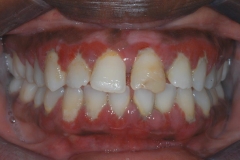

This young patient was self-conscious about the appearance of her short teeth and gummy smile. Through crown lengthening and tooth whitening procedures, we were able to create a beautiful, more mature smile.